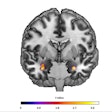

At the one-year follow-up, the researchers found higher average R2* values within the substantia nigra after a supratentorial infarction, "a finding that we interpret as iron accumulation as a result of neurodegeneration," they wrote. In addition, R2* maps consistently showed higher substantia nigra R2* values (iron concentration) when the infarct occurred at the ipsilateral striatum compared with R2* values when the infarct occurred in other locations. In other words, R2* mapping of iron content also could be used to image neurodegeneration remotely, if strokes were to occur in disconnected areas.

"This finding could be clinically useful because it shows that a simple magnetic resonance imaging method such as R2* can provide a more comprehensive picture of the consequences of an infarct," added Dr. Thomas Tourdias, PhD, study co-author and professor of radiology, in a statement.